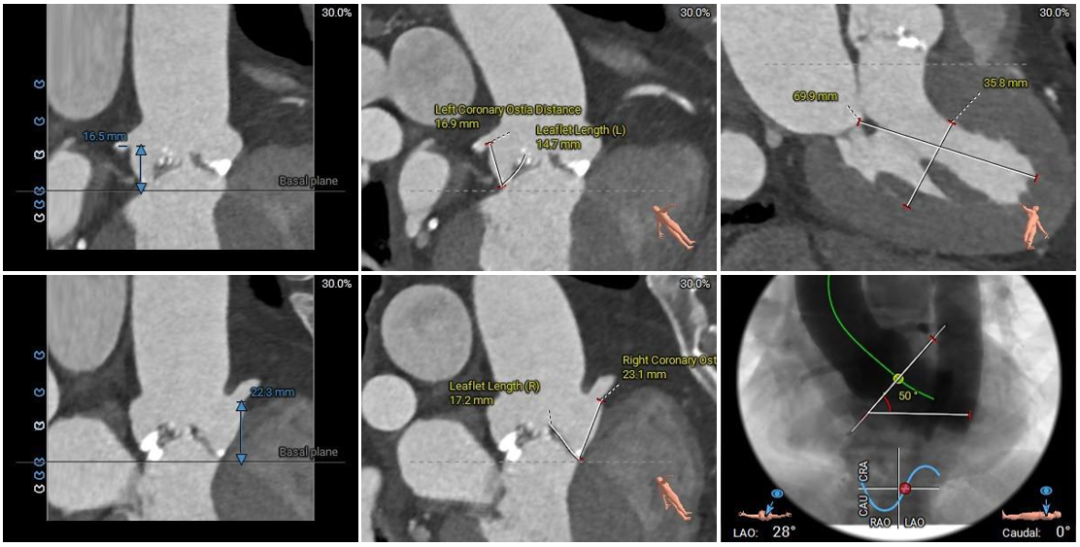

术前CT评估:

本例患者为主动脉瓣重度狭窄伴中度反流,因反复严重心衰伴心绞痛多次住院,同时合并高血压病、陈旧性脑梗死等基础疾病,一般状况不佳,无法耐受外科开胸手术,有强烈的微创换瓣手术意愿;患者术前心脏彩超、CT等评估适宜行TAVR手术,TAVR手术指征明确。CT分析提示患者为Type1型二叶式主动脉瓣,瓣叶明显增厚伴重度钙化,左右窦间可见钙化融合嵴,瓣膜植入后受钙化嵴挤压影响存在瓣周漏风险;此外,患者左窦间存在长条状钙化延伸至瓣环下10mm水平,瓣膜植入后可能压迫传导束,存在起搏器植入风险,对瓣膜释放位置及精准度要求较高,需要术者快速、精准的操作能力及手术团队的密切配合。

手术过程中,在完成跨瓣操作后,23mm球囊预扩有轻微腰征、无造影剂渗漏,预装TaurusElite AV29瓣膜到位,输送系统快速、顺利地完成过弓、跨瓣操作,于瓣环上约2mm定位释放;针对本例患者瓣叶明显增厚伴重度钙化,左右窦间可见钙化融合嵴的特点,TaurusElite瓣膜高密度流入端设计提供了足够的径向支撑力,保证了瓣膜的锚定力,瓣膜内外双裙边设计能提供良好的辅助锚定力,有效减少瓣周漏。此外,本例患者左窦间存在长条状钙化延伸至瓣环下10mm水平,释放位置偏深可能存在起搏器植入风险,TaurusElite瓣膜具有多次完全可回收,回收后可重新跨瓣、释放的特点,给予术者足够的信心完成高位释放的操作,释放后最终瓣架底端位于瓣环下约1mm,实现了释放位置的精准控制,有效的减少了起搏器植入风险,确保了手术安全、顺利的完成。这例手术为永州地区开展的第一台TAVR手术,填补了该地区TAVR技术空白,标志着永州市心脏瓣膜疾病诊治迈入了全新的微创治疗时代!